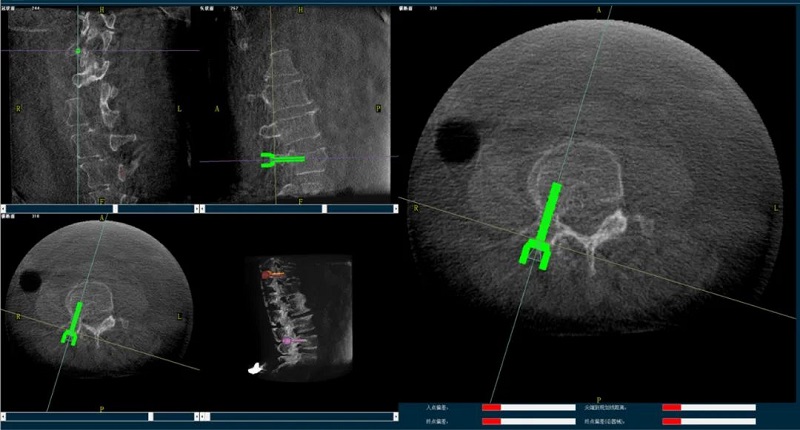

骨科手術(shù)機器人輔助下椎體成形術(shù),是以手術(shù)機器人智能機械臂為基礎(chǔ),仿照經(jīng)皮骨水泥椎體成形術(shù)的施術(shù)步驟,限定穿刺點、穿刺方向、角度和深度,使穿刺針經(jīng)過安全路徑進入目標區(qū)域,然后進行骨水泥注入,輔助手術(shù)設(shè)計、精準指導手術(shù)實施。以普愛醫(yī)療的骨科手術(shù)機器人為例,其輔助進行的一例胸腰椎壓縮性骨折經(jīng)皮椎體成形術(shù)的過程如下:

(1)首先使用普愛醫(yī)療三維C形臂采集胸腰椎病灶三維圖像,對傷椎進行三維重建;

(2)醫(yī)生制定個性化的手術(shù)方案,在機器人導航界面上進行路徑規(guī)劃;

(3)根據(jù)設(shè)定好的的位置和入針方向,植入引導針;

(4)所有引導針植入完畢后,沿引導針方向進行椎弓根及椎體置管,建立通道;

(5)沿通道注入骨水泥,恢復椎體高度,并觀察其擴散情況,達到滿意效果后,停止注入骨水泥。